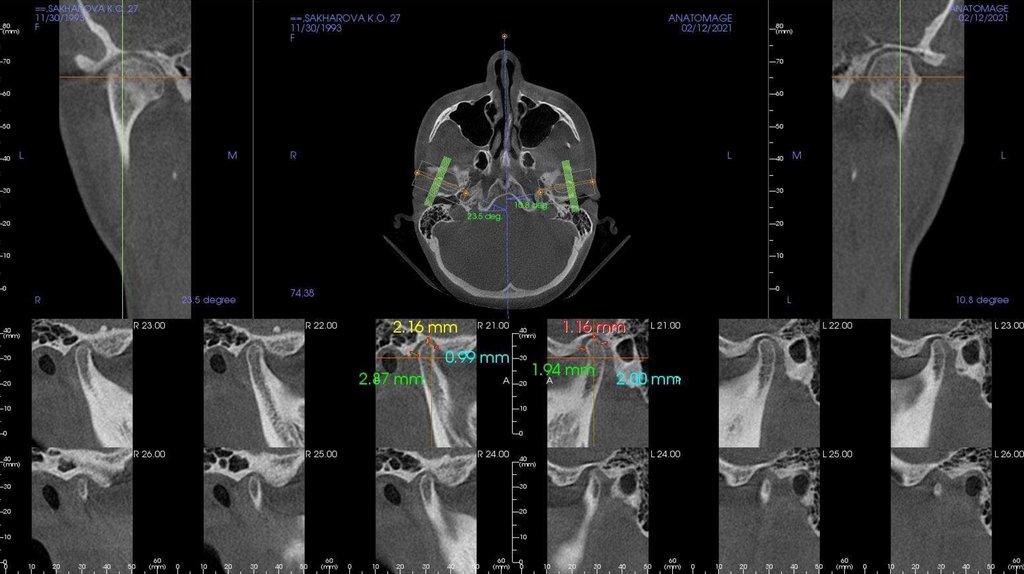

По рассчетам снимков:

• Ретрузия резцов верхней челюсти

• Компрессия головок суставов, особенно правого( началось

ремоделирование)

• Костная ассиметрия(10 мм)

• 2 класс